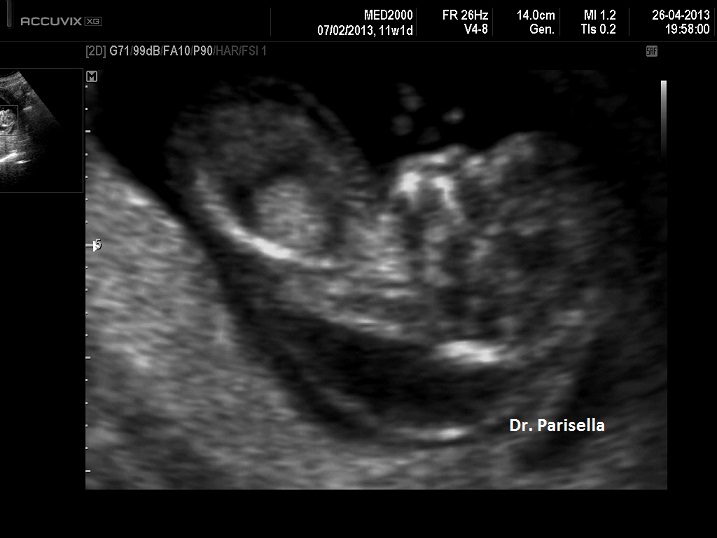

I segni principali sono la micromelia marcata, l'idrope fetale e ossificazioni ectopiche.

1. micromelia severa